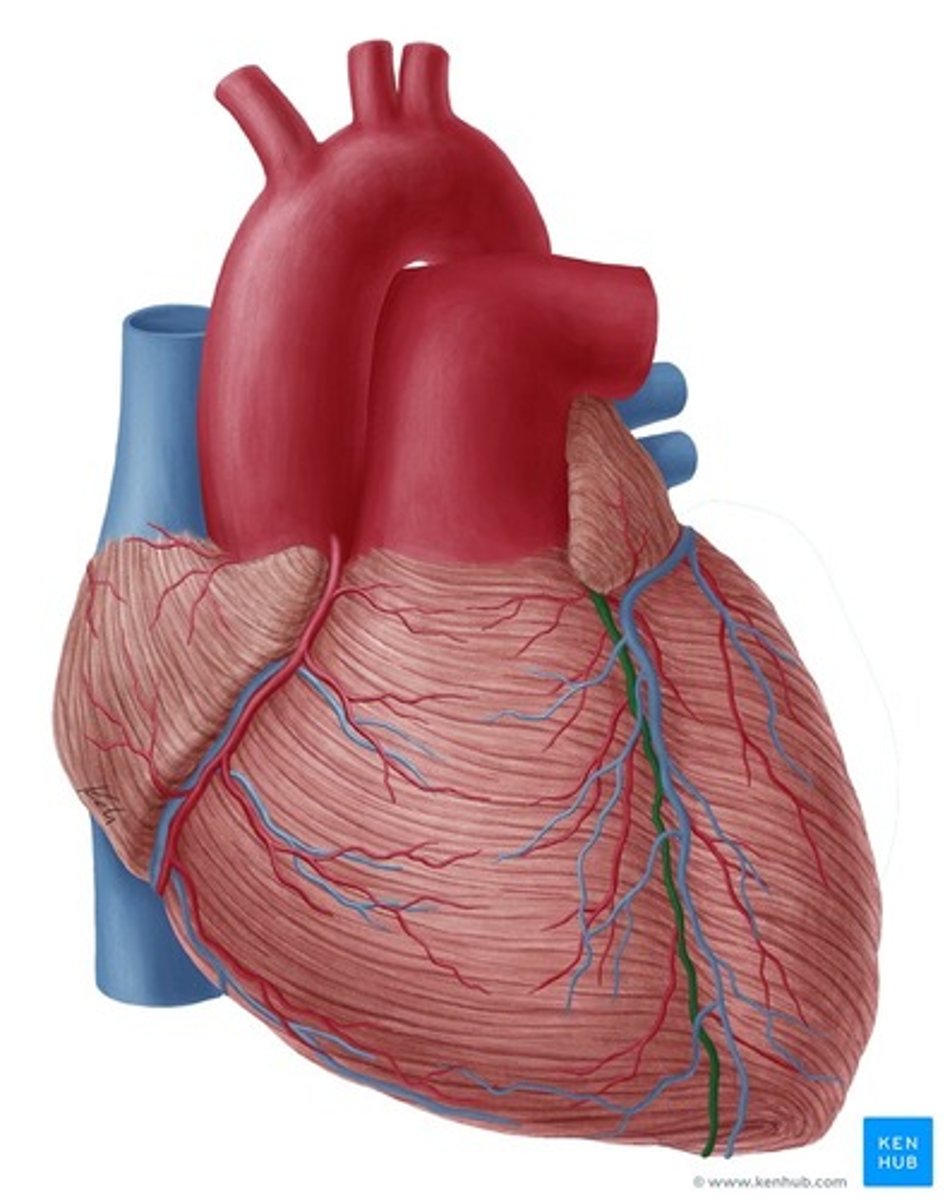

bruzda międzykomorowa tylna

posterior interventricular sulcus

Jak biegną bruzdy międzykomorowe?

od bruzdy wieńcowej w kierunku koniuszka serca

Co tworzą bruzdy międzykomorowe w okolicy koniuszka serca?

wcięcie koniuszka serca

wcięcie koniuszka serca

notch of cardiac apex